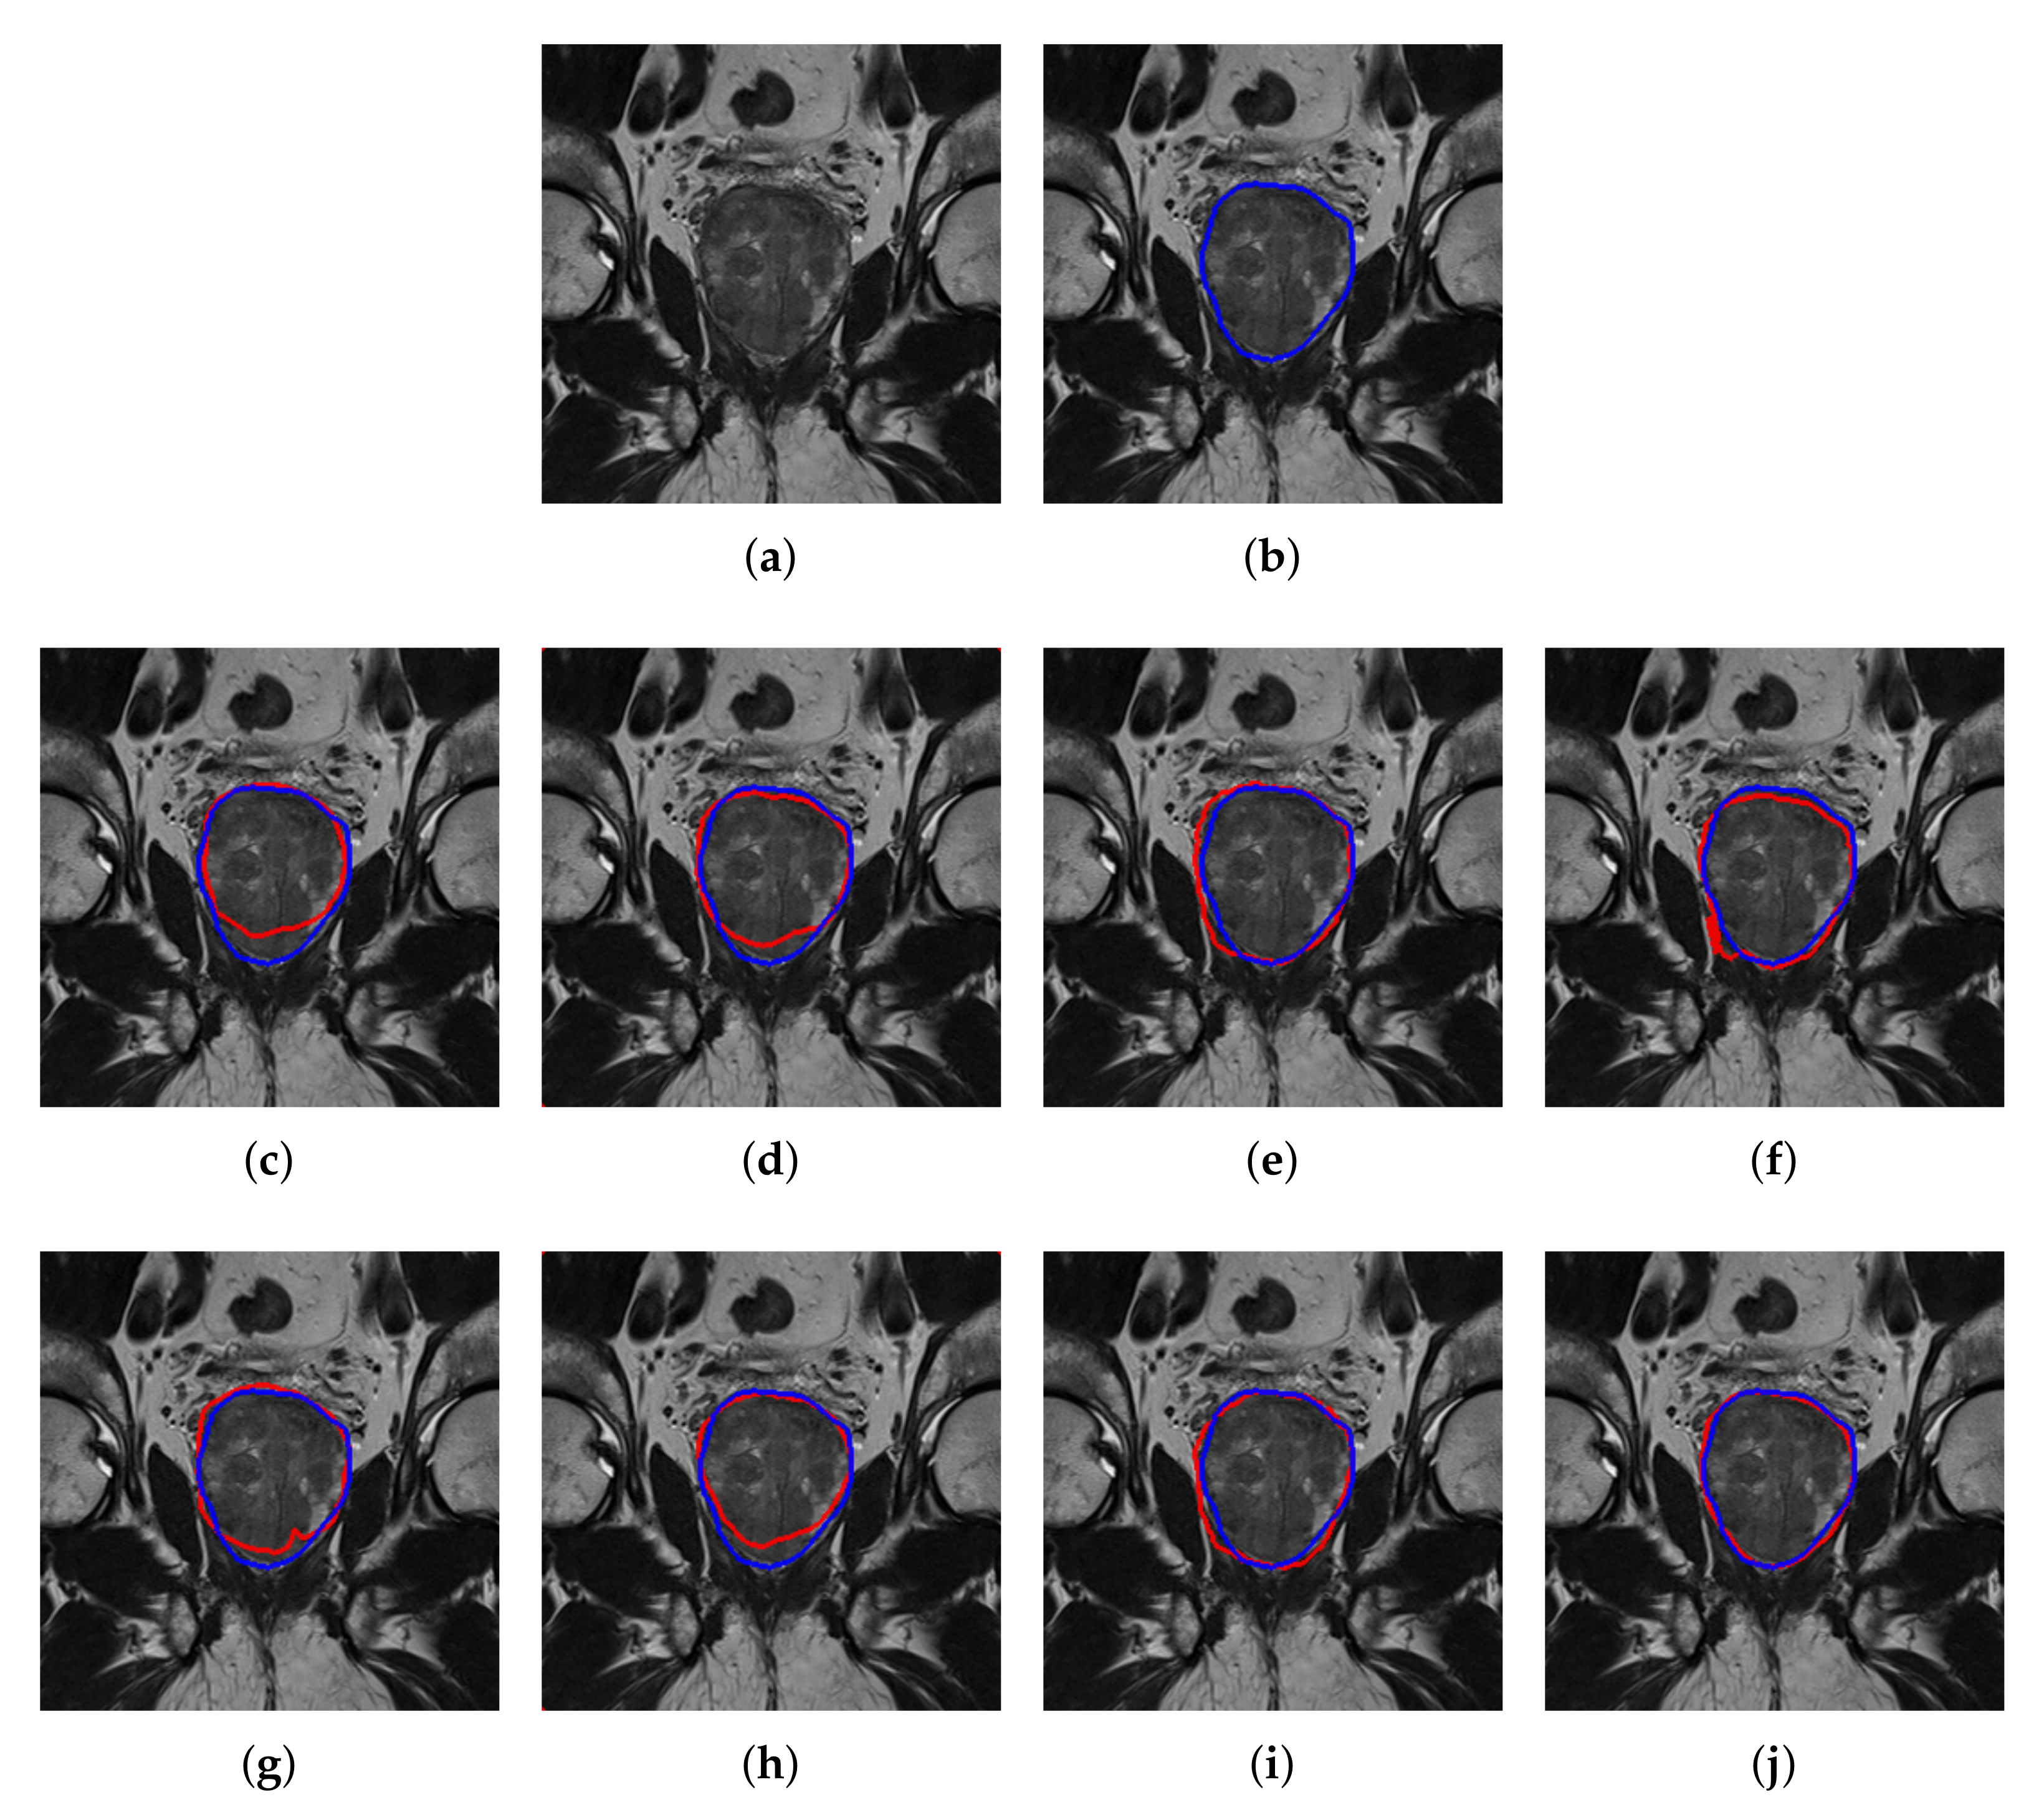

4.2. Quantitative and Qualitative Performance